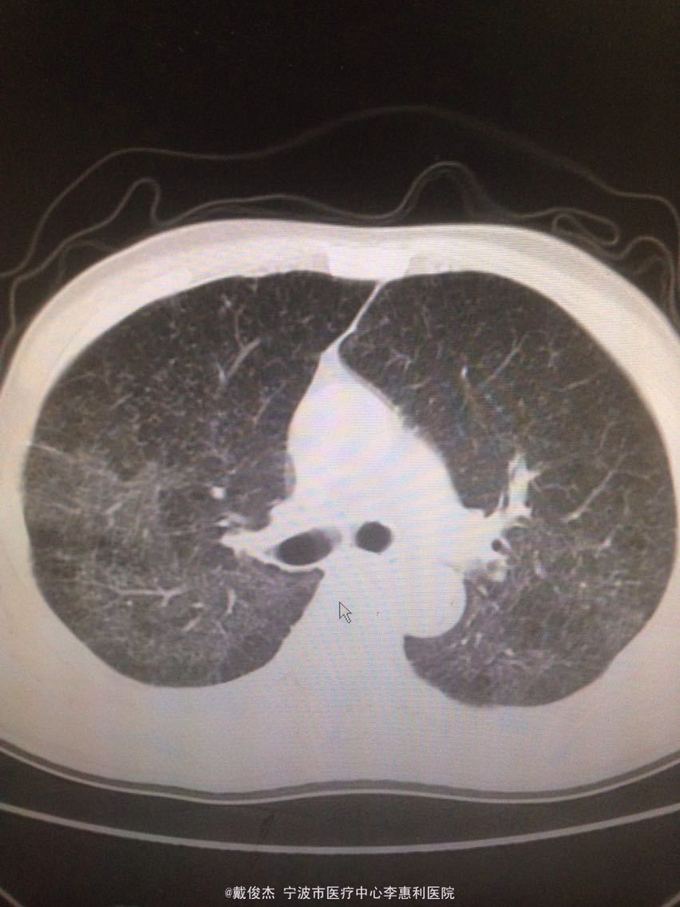

患者,男,主诉:反复发热2月,再发伴头痛12天 病史:2月前出现发热,伴咳嗽、咳痰,12天前出现头痛

查体:神志清,双肺啰音,颅神经阴性,颈抵抗,四肢肌力正常,双巴氏征阴性 辅查:脑脊液压力380mmH2O,细胞4100/ul,多核90%,单核10%,蛋白223mg/ml。胸部CT示:两肺多发粟粒小结节。头颅MRI示:双侧大脑半球、脑干、小脑多发病灶。

诊断:结核性脑炎,肺结核 处理:抗痨治疗,激素,降颅压,保护神经和对症支持治疗

该患者考虑肺结核致结核性脑炎